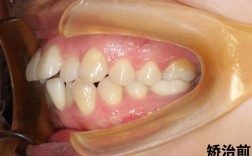

牙齿问题的复杂程度是最核心的影响因素,牙齿畸形可分为简单性和复杂性两类:简单性畸形主要表现为轻度拥挤、少量间隙或单纯牙列不齐,这类问题通常牙根位置正常、颌骨发育无明显异常,通过常规矫正即可解决,时间相对较短,一般1.5-2年,青少年因替牙障碍导致的轻度前牙拥挤,通过拔除1-2颗前磨牙为牙齿排齐提供空间,配合固定托槽矫正,通常1年半左右可完成,而复杂性畸形则涉及骨性问题(如上颌前突、下颌后缩)、严重拥挤(需要拔除4颗前磨牙甚至更多)、开颌、深覆合等,这类问题不仅需要移动牙齿,还需调整颌骨关系或改善面部肌肉功能,矫正难度显著增加,成人骨性上颌前突伴牙列严重拥挤,可能需要通过正畸-正颌联合治疗(即先通过矫正调整牙齿位置,再通过手术调整颌骨位置),总周期可能延长至3-5年;即使是单纯的严重拥挤,若牙根形态异常(如弯曲、融合牙)或存在埋伏阻生牙,也需要额外时间进行助萌或牵引,矫正周期可能达到2.5-3年。